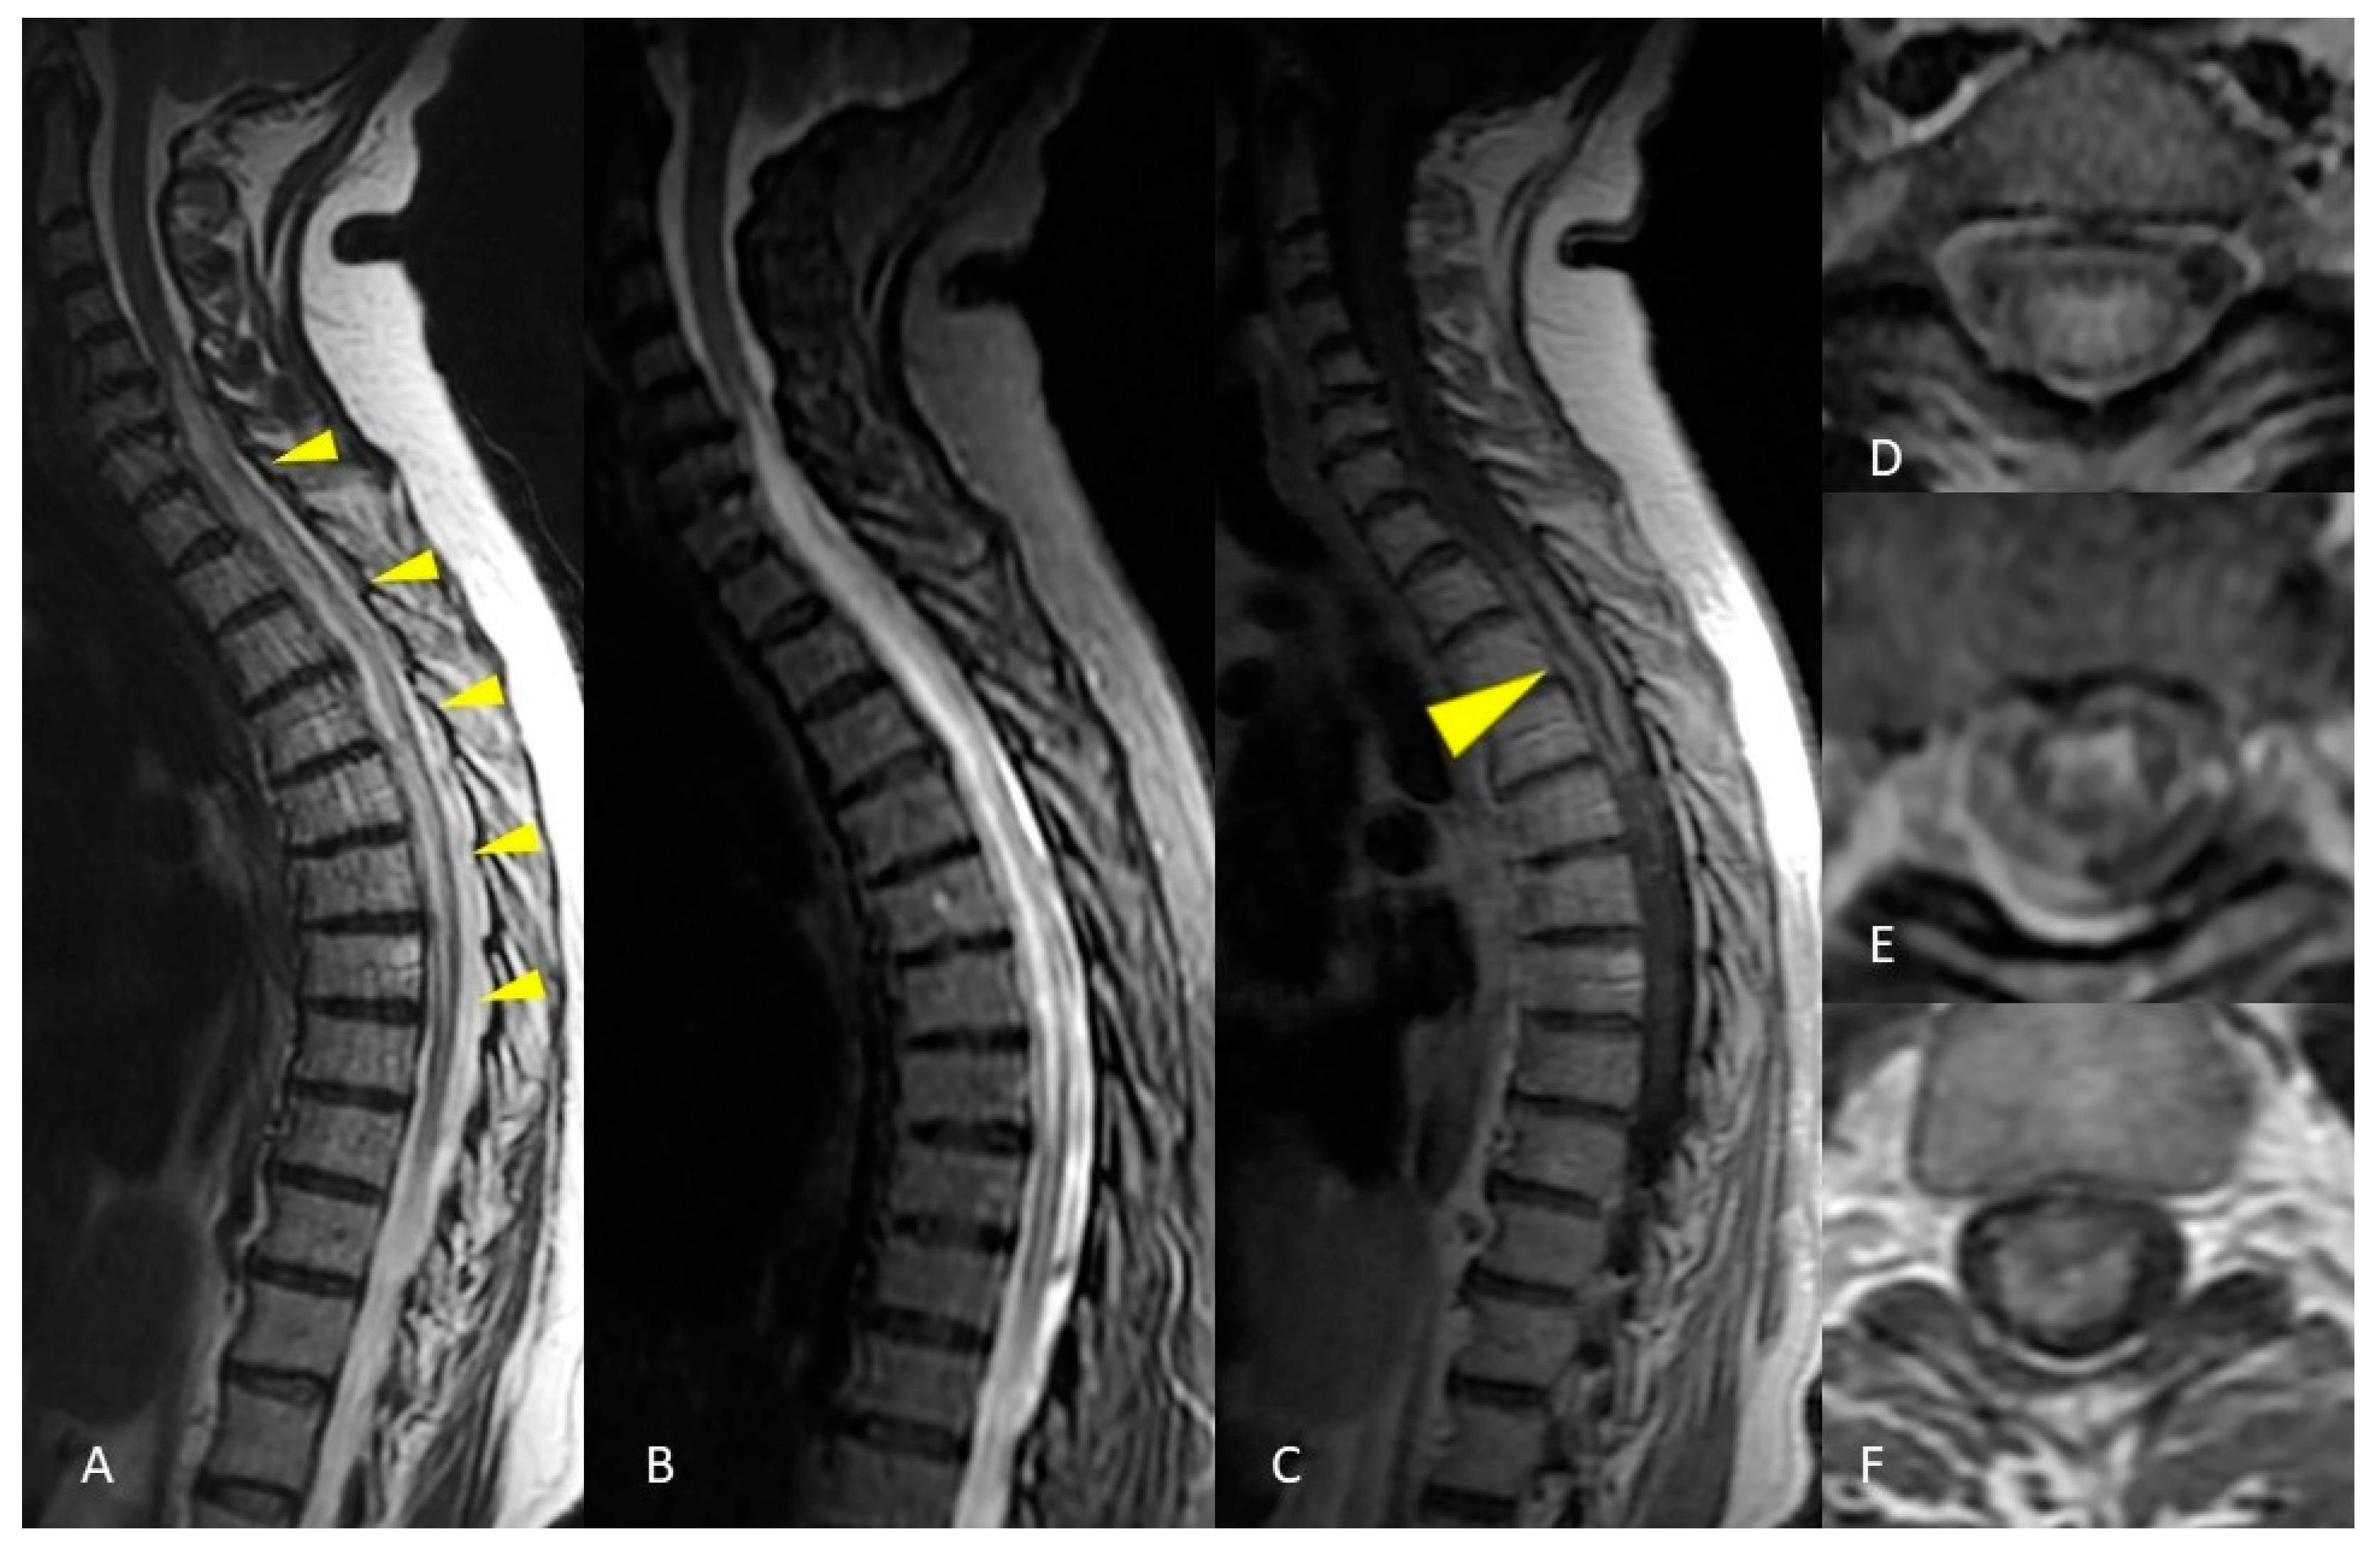

2.1. Case Presentation 1

3.4. Idiopathic Transverse Myelitis